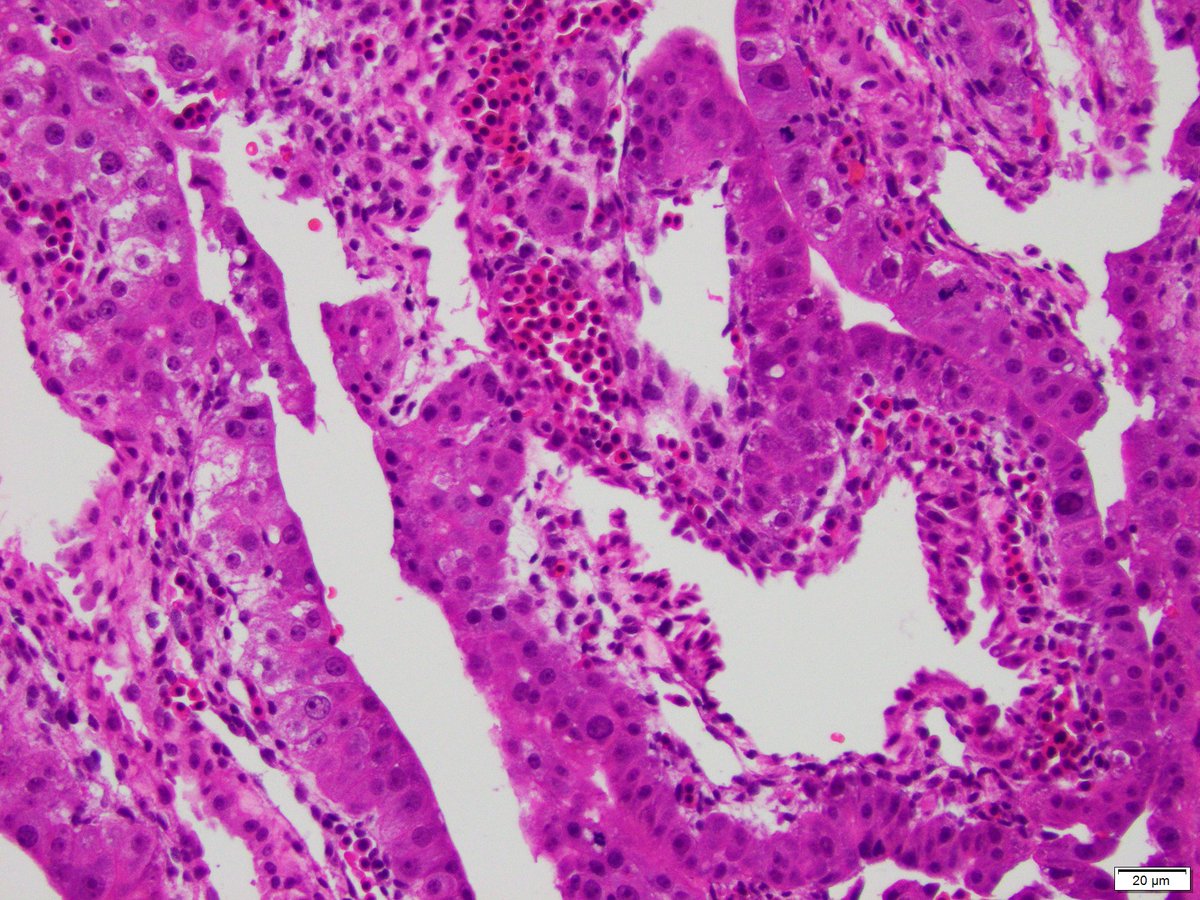

Incidental finding in an ectopic pregnancy resected at 6 weeks. What is it? 4x, 10x, & 20x Kyla Jorgenson and Ben Gertsen were there when I took the pictures, so they should let others have a chance. #Pedipath #Pathtwitter #Path2Path #Embryo #MedStudentTwitter